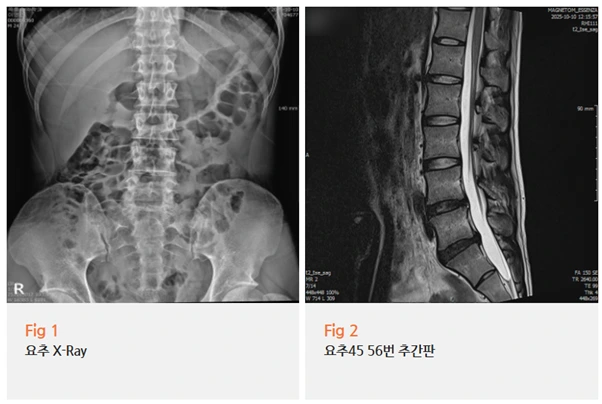

결과는 요추 4-5번, 요추 5번-천추 1번 사이의 추간판 팽윤이었어요.

%EA%B7%B8%EB%A6%BC2.png?type=w966

추간판 탈출증이라고 흔히 부르는 '디스크'는

추간판이 신경관 쪽으로 실제로 터져 나온 상태를 말하는데,

추간판 팽윤은 그보다 이전 단계로, 디스크가 전체적으로 부풀어 오른 상태입니다.

터지지는 않았지만, 이미 신경 주변을 압박할 수 있는 상태라는 거죠.